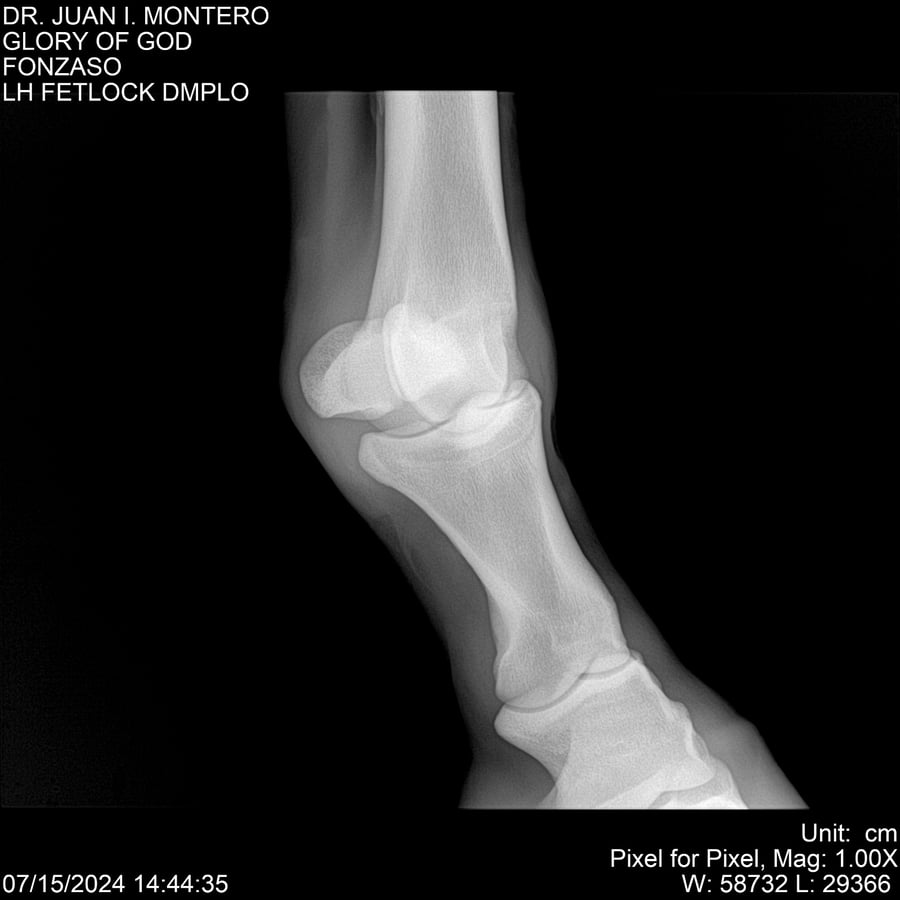

LOTE 10, GLORY OF GOD 🔥 🔥 🔥 Lote Anterior Volver al remate Lote Siguiente Ficha Contacto Montevideo - Ficha del Lote Identificador: #281389 Categoría: Yeguarizos Montevideo - 115 Visualizaciones ClicData Contacto Empresa: Abelenda N. R., Walter Hugo Nombre*: Teléfono* : E-mail* : Mensaje Enviar Registrese gratis Este contenido Exclusivo está disponible sólo para usuarios registrados Ingresar